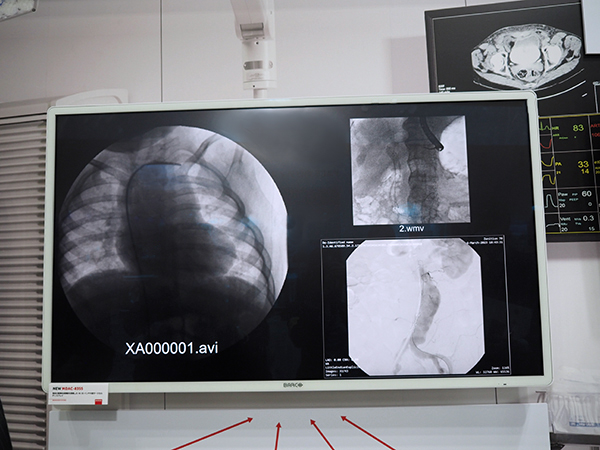

また,画像配信ソリューションコーナーでは,画像取り込みから表示まで,4K解像度,非圧縮,低遅延で画像をIP伝送する「Nexxis」による映像配信環境を紹介。独自の画像合成機能を搭載した4K 55インチ大型サージカルディスプレイ「MDAC-8355」,4K3D表示を可能にする55インチ大型サージカルディスプレイ「MDFC-8255 3SB」が加わったことがアピールされた。

独自の画像合成機能を搭載した4K 55インチ大型サージカルディスプレイ「MDAC-8355」